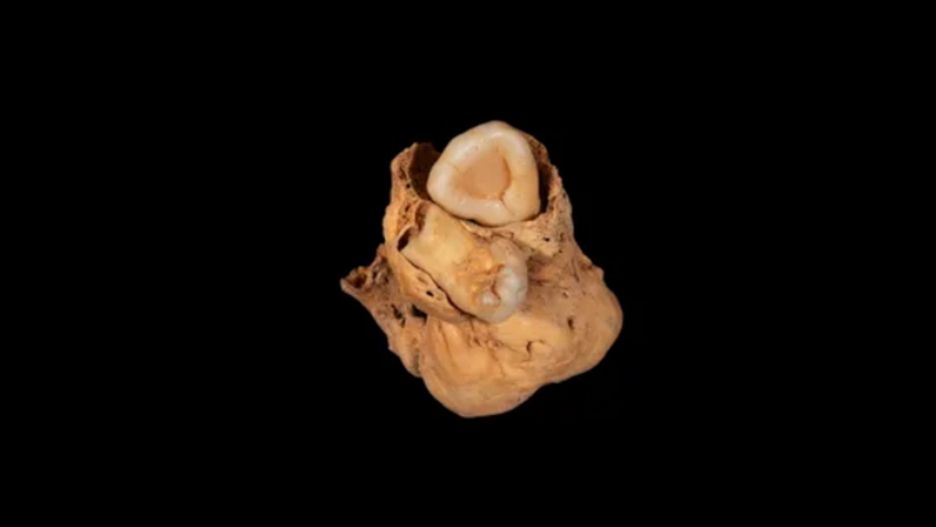

Potworniak z EgiptuPotworniak z Egiptu

Źródło zdjęć: © Licencjodawca | A. Deblauwe, Amarna Project

Podczas wykopalisk archeolodzy zauważyli w miednicy kobiety coś niezwykłego: masę kostną wielkości dużego winogrona z dwoma wgłębieniami, w których znajdowały się zdeformowane zęby. Obecność zębów i lokalizacja w okolicy miednicy wskazywały, że był to potworniak jajnika.